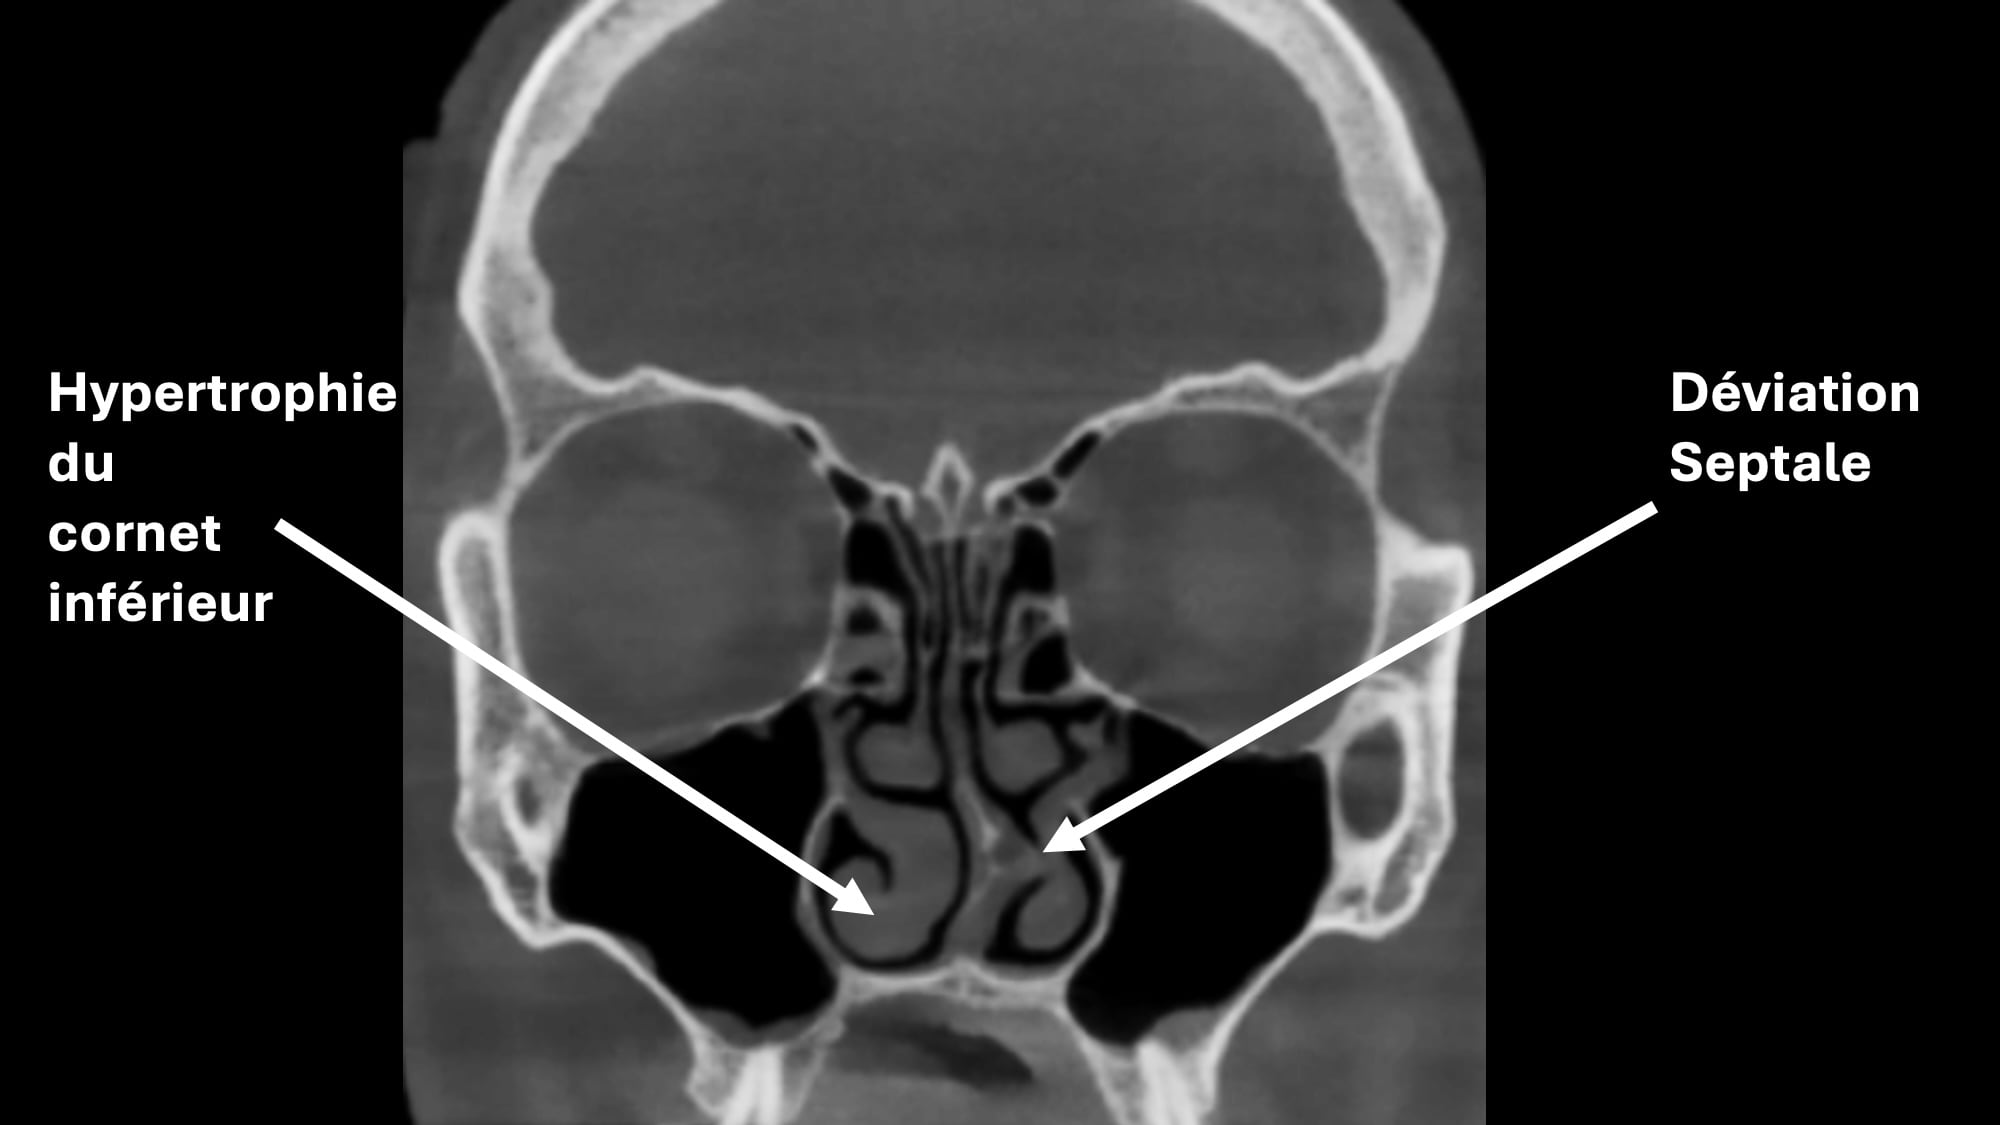

Cloison nasale déviée

Une déviation de la cloison nasale peut gêner la respiration, surtout d’un seul côté. Cette anomalie est souvent d’origine congénitale ou due à un traumatisme nasal.

Le traitement est chirurgical : il s’agit d’une septoplastie, qui permet de redresser la cloison

Hypertrophie des cornets

Les cornets sont des structures osseuses recouvertes de muqueuse qui peuvent augmenter de volume, notamment en cas d’allergies ou de sinusite chronique, rendant la respiration nasale difficile.

Les traitements sont les sprays nasaux à base de corticoïdes ou en cas d’échec du traitement médical, une réduction du volume des cornets par radiofréquence